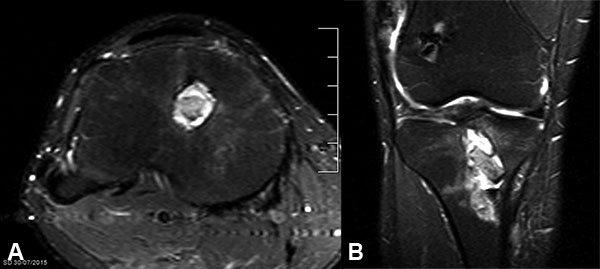

La anatomía patológica informó 12 quistes sinoviales, 2 de ellos asociados a fibrosis y 5 a remanentes de sutura, y 2 casos únicamente fibrosis (Tabla 3). Respecto a las recidivas, se excluyeron 3 pacientes para el análisis al año de seguimiento. Un paciente (9%) evolucionó con 3 recidivas. El quiste post reconstrucción de LCA fue operado en otro centro mediante una resección simple, sin relleno óseo del túnel tibial. La primera recidiva fue a los 2 meses de la resección, y se trató también en otro centro con aspiración por punción del quiste. Nos fue derivado 2 meses posterior a la punción por una segunda recidiva. Se realizó entonces una resección y relleno del túnel con 3 cilindros de hueso autólogo obtenido de la metáfisis femoral con un sistema de mosaicoplastia. El quiste presentaba entonces paredes bien definidas, con contenido seroso en su interior (fig. 4a). La histología confirmó el diagnóstico de quiste sinovial (fig. 4b). Cuatro meses luego de la cirugía sufrió una nueva recidiva (tercera). En radiografías y RM se apreciaba el agrandamiento del túnel con el taco óseo en su interior y la presencia del quiste (fig. 5). Se decidió en este caso una re-operación con un curetaje extenso del túnel, se resecó toda la pared del mismo que se había “corticalizado” y luego se rellenó de la cavidad utilizando hueso de banco.

Figura 5: A y B) Imagen de RM. Se observa el taco óseo dentro del quiste luego de la 3er recidiva.